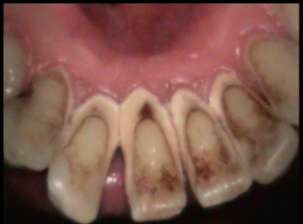

Intraoral Photograhs

Class I